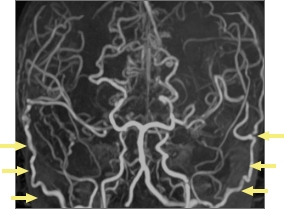

4歳女児症例 脳MRA検査

両側STAMCAバイパス術後